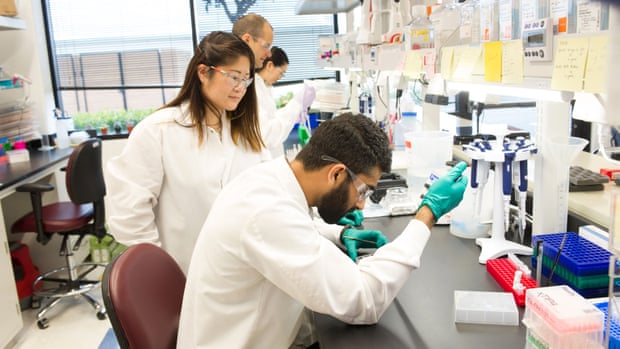

Gazetinin haberine göre; 2000'lerin başlarında, Kaliforniya, Stanford Üniversitesi'nden bir grup bilim insanı, 1950'lerde parabiyoz olarak bilinen şok edici bir deneyi yeniden canlandırdı.

Yaşı küçük olan yaşlı fareleri eşleştirdiler, derilerini soyup yanlarını diktiler, böylece iki hayvan aynı kan dolaşım sistemini paylaştılar. Bir ay sonra, eski farelerin kaslarında ve karaciğerlerinde gençleşme belirtileri buldular.

2005 yılında yayınlanan bulgular, bilim insanlarının, girişimcilerin ve halkın zihinlerini yaşlanan insanları gençleştirmek için genç kan potansiyeline çevirdi.

Birçok girişimcinin bir arada yaşamanın sırlarını keşfetmeye çalıştığını ve bunları plazmada yaşla birlikte değişen faktörleri belirleyerek yaşa bağlı hastalıkları tedavi etmek için kullandığını belirtti.

Alkahist Laboratuvarı da, genç kanın canlandırıcı etkisini gösteren bir makale yayınladı. Genç kan nakli yapılan yaşlı farelerde, bilişsel görevlerinde iyileşme gösterdi. Yeni nöronlar büyüdü ve çalışması kan plazmasındaki proteinler büyük ölçüde sorumlu olduğundan genç plazmanın faydalı bir etkiye sahip olduğunu gösterdi.

Alkahist Laboratuvarı geçen yıl Ağustos ayında, hafif ila orta derecede Alzheimer olan 40 hastanın altı aylık bir çalışmasının sonuçlarını bildirdi. İnsan plazmasının "bir kısmı" implante edildi ve beklenen zihinsel bozulmayı durdurduğu ortaya çıktı.